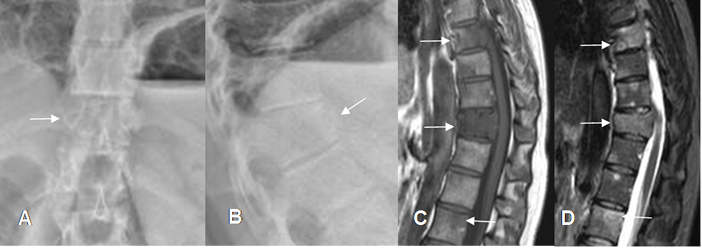

Fig 154 A. Metástasis lítica.

A: Rx AP y B: Rx lateral. Pérdida en la nitidez de los contornos en D12.

C: RM sagital en T1 y D: RM sagital en STIR. Además de D12, se encuentran lesiones que comprometen otros cuerpos dorsolumbares, por enfermedad metastásica.